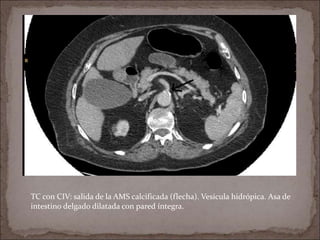

TC con CIV: salida de la AMS calcificada (flecha). Vesícula hidrópica. Asa de

intestino delgado dilatada con pared íntegra.